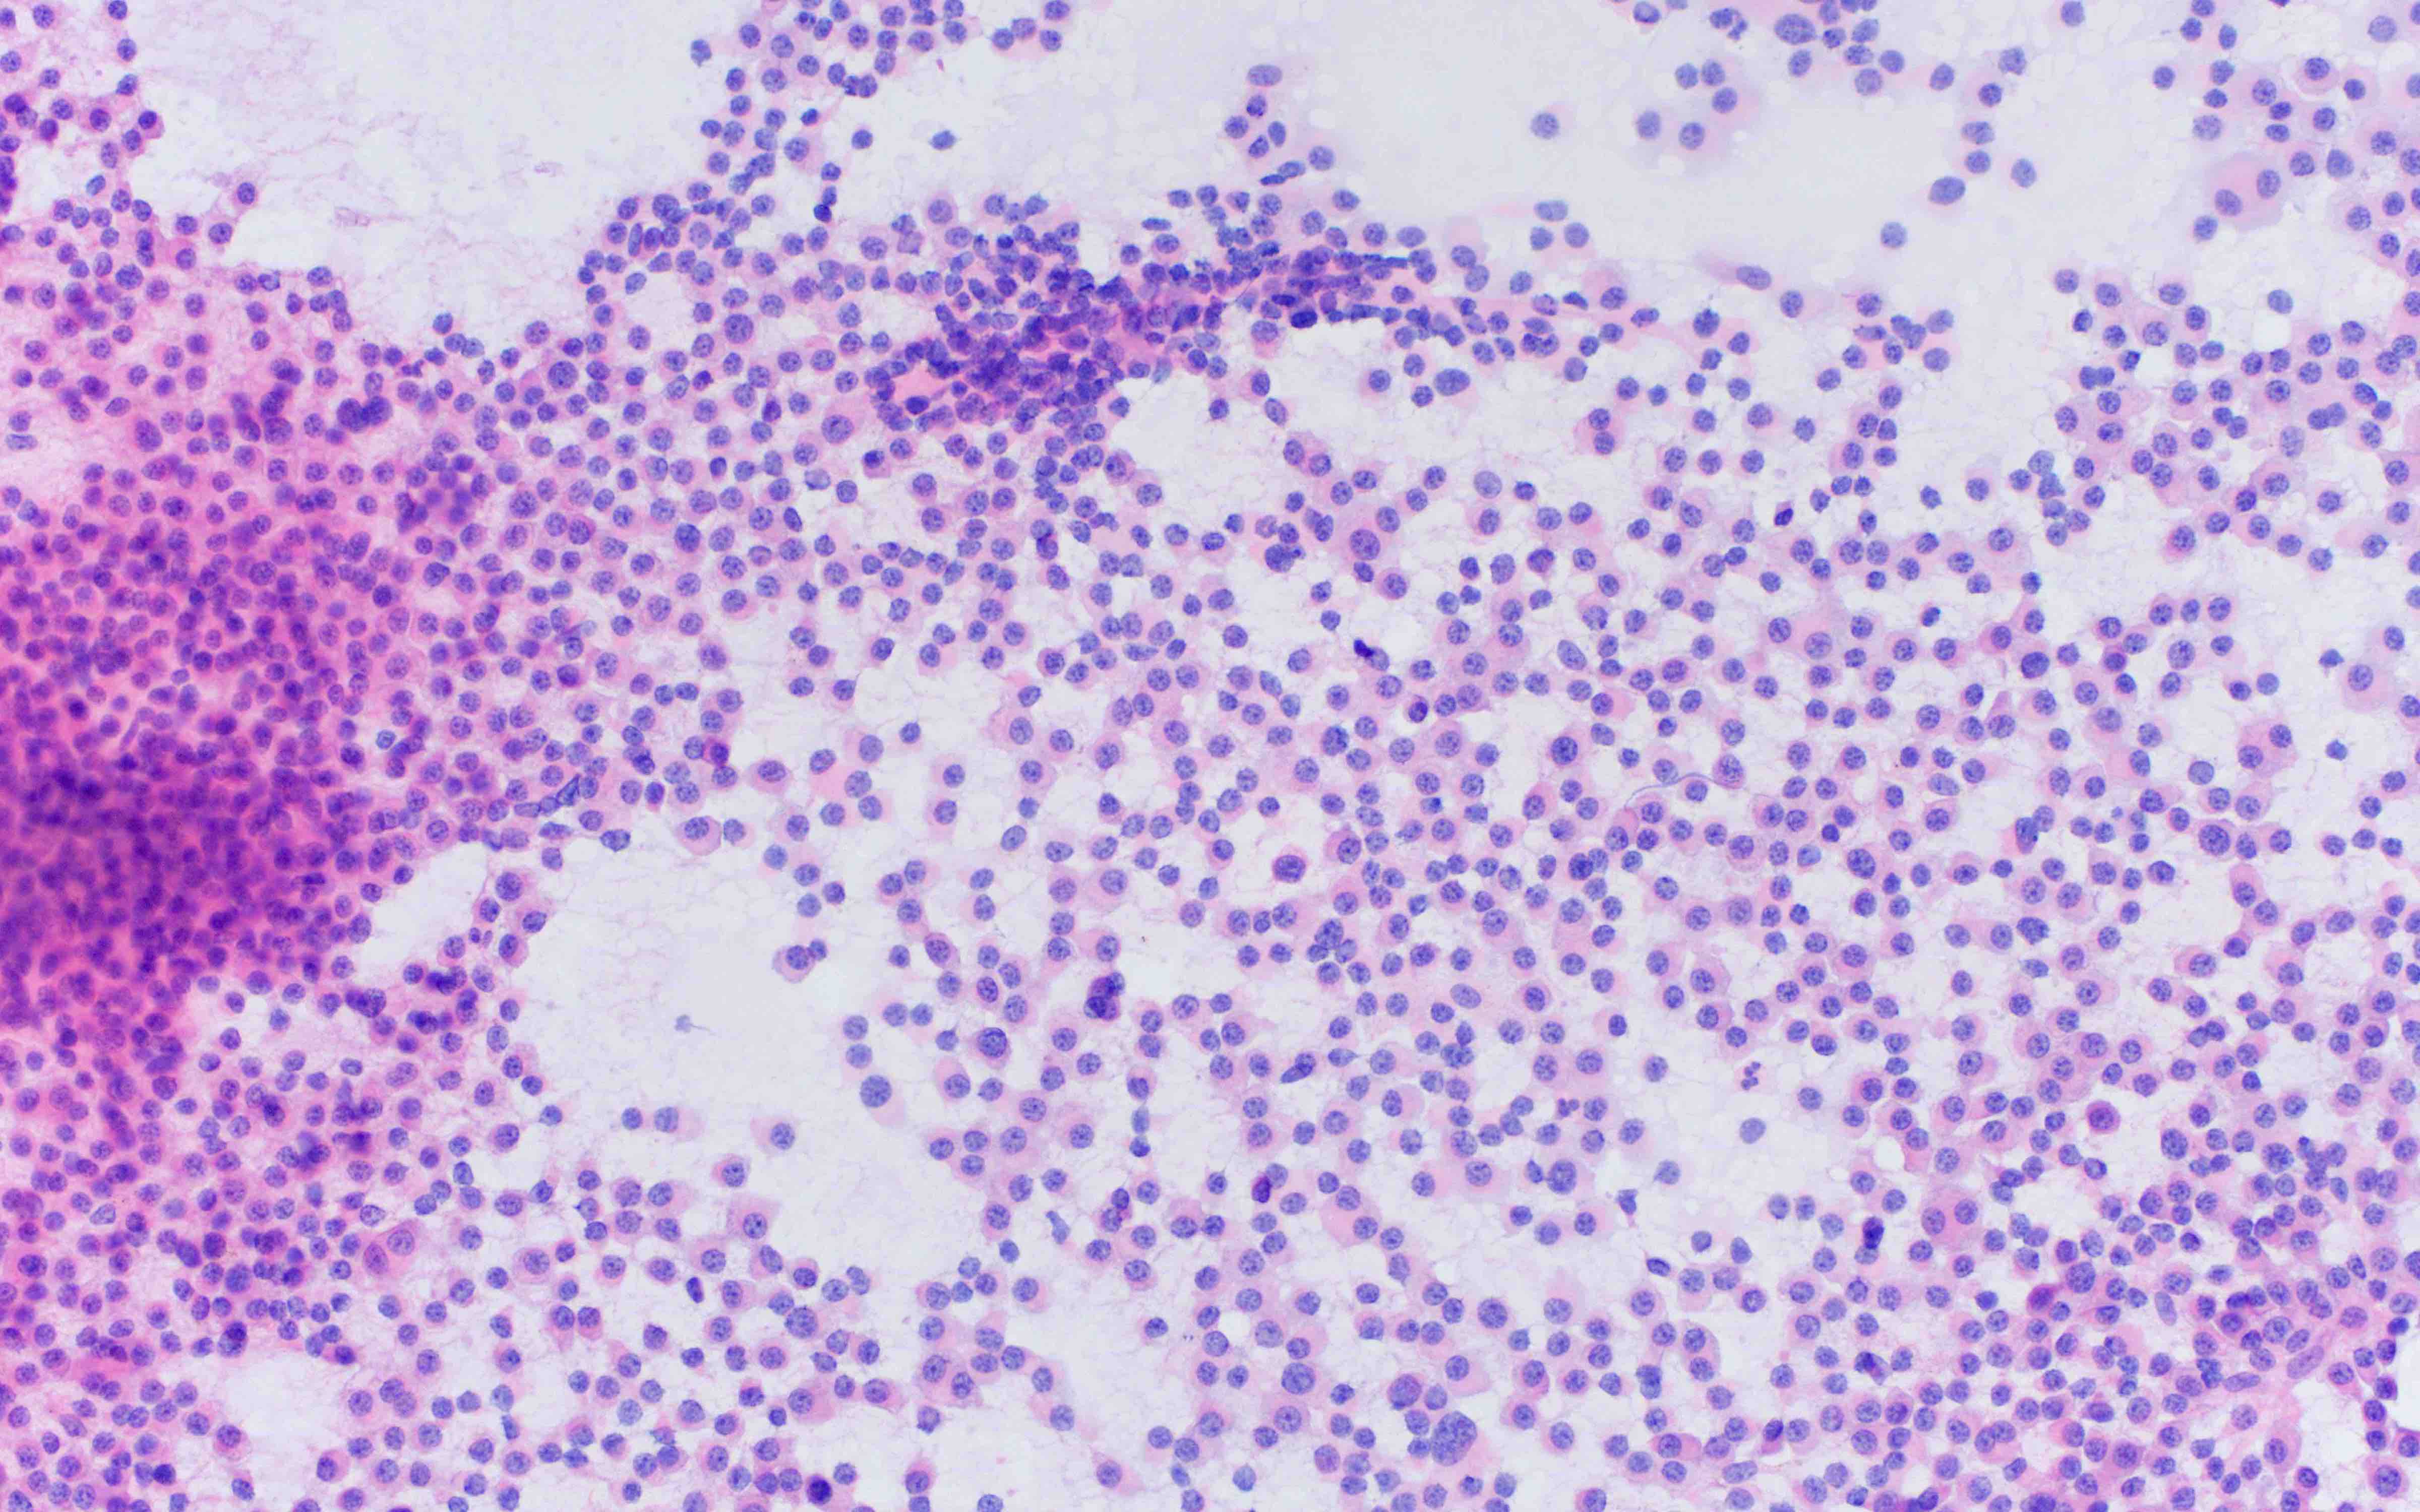

Cytology description

- Cytology can assess plasma cell morphology (e.g., mature, immature, plasmablastic) but number of plasma cells present may vary substantially from the core biopsy

- Mature plasma cells: oval with abundant basophilic cytoplasm, perinuclear hof, round eccentric nuclei, clock face chromatin and indiscernible nucleoli

- Immature plasma cells: higher nuclear to cytoplasmic ratio, more abundant cytoplasm and hof region compared to plasmablastic, more dispersed chromatin, often prominent nucleoli

- Plasmablastic: less abundant cytoplasm with little or no hof region, fine reticular chromatin, large nucleus (> 10 microns) or large nucleolus (> 2 microns) (Blood 1998;91:2501)

- Pleomorphic: multinucleated, polylobated

- Rare cases may have small, lymphoid appearing plasma cells or plasma cells with marked nuclear lobation

- Immature or pleomorphic features are rare in reactive plasma cell proliferations

- Morphologic features:

- Mott cells / morula cells: multiple grape-like cytoplasmic inclusions comprised of crystalized immunoglobulin

- Russell bodies: hyaline intracytoplasmic inclusions

- Flame cells: vermillion staining glycogen rich IgA in cytoplasmic projections (American Society of Hematology: Flame Cells in Multiple Myeloma [Accessed 26 May 2022])

- Pseudo-Gaucher cells / thesaurocytes: overstuffed fibrils (J Clin Pathol 1976;29:916)

- Cytoplasmic crystals: occasional in myeloma, common in adult Fanconi syndrome (Am J Clin Pathol 1983;80:224)

- Dutcher body: pale staining immunoglobulin filled cytoplasm invaginating into the nucleus and appearing as an intranuclear inclusion, single and usually large, more common in IgA myeloma